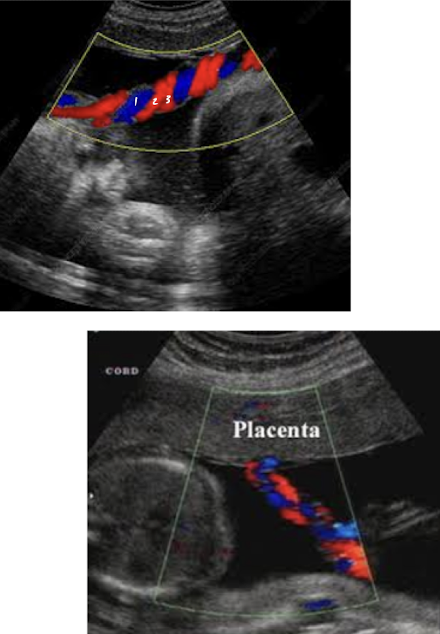

umbilical cord color Doppler

color Doppler is used to visualize umbilical arteries and vein

the bladder, when full, is seen between 2 umbilical arteries

umbilical cord should be images in cross section and with color Doppler at level of bladder to confirm the number of cord vessels